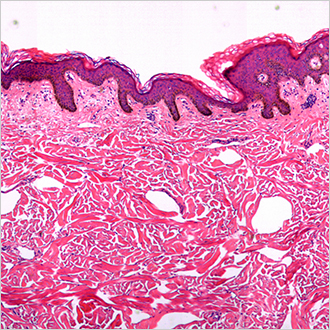

TM-Microscopy

Cette solution permet d'optimiser la diffusion et l'accès aux images d'anatomopathologie en récupérant, stockant et diffusant ces images via la visionneuse TM-Microscopy. Elle garantit des diagnostics de haute qualité grâce à une meilleure pertinence du diagnostic des échantillons et à un meilleur échange entre les pathologistes. En savoir plus ?